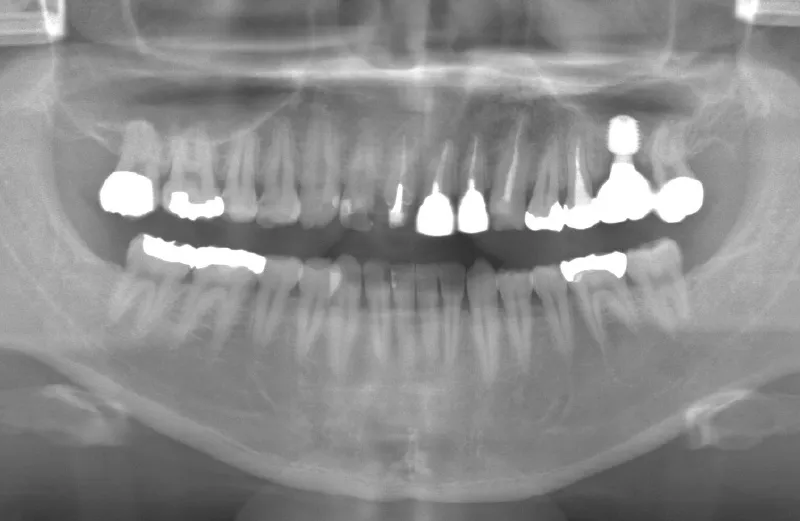

メガジェンオペの症例紹介03

治療前

治療後

| 主訴 | 他院では左上6は歯根が割れており、保存出来ないと言われた。 歯を削りたくないのでブリッジは嫌でインプラント治療を希望するも歯の根の先に骨が少なく、抜歯後しばらく待ってからサイナスリフトが必須であり、インプラント治療に1年以上かかると言われたのでセカンドオピニオンを希望で来院。 |

| 治療期間 | 2.5ヶ月で仮歯が入り、 4ヶ月で最終補綴物が入って終了。 |

| 治療費 | 約550,000円 |

| 治療内容 | エクストラワイドショートインプラントを埋入し、上顎洞を移植材を用いずに挙上しインプラントを埋入した。約2.5ヶ月で仮歯を装着し、様々な機能面に問題がないことを確認し4ヶ月で最終補綴物を装着して終了した。 |

| 治療の リスク |

インプラント埋入オペ時に術者が上顎洞内にインプラントを迷入させる可能性がある。これは術者が技術的に熟練していれば防ぐことが可能。 |